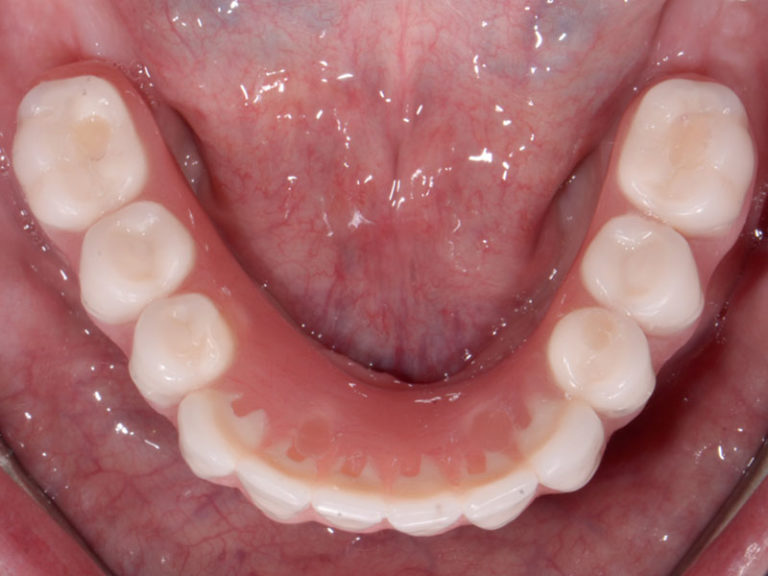

Yes, modern dentures are designed to mimic natural teeth with realistic shapes, textures, and shading, creating a natural and aesthetically pleasing smile.

- Implant-supported dentures – Attach to implants for better stability.

Full dentures rely on suction and adhesives, while partial dentures attach to remaining teeth with clasps. Implant-supported dentures provide maximum stability without slipping.